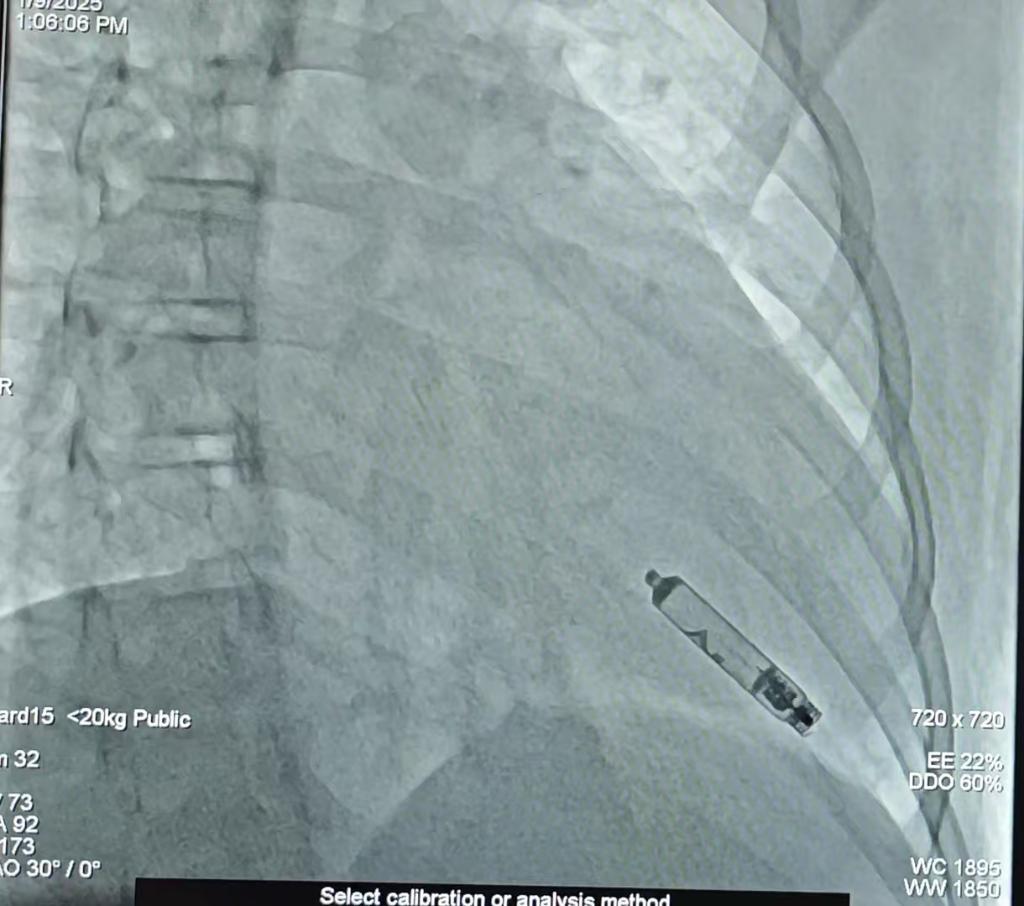

图为无导线可回收心脏起搏器植入后影像图。重庆医科大学附属儿童医院供图

据了解,该新型起搏器长度仅3.8厘米,直径6.5mm,重量仅2g,通过头端1.63mm的螺旋电极旋入心肌发挥起搏作用,为儿童患者缓慢性心律失常的起搏治疗带来了更大的益处。与传统起搏器相比,其优点在于仅通过微创方式经股静脉将起搏器植入右心室,无需切开皮肤及导线;此外,该起搏器电池耗尽后亦可通过微创方式回收,使用寿命为17到20年。

今年1月9日,吕铁伟带领心血管科心律失常医护团队,经过一系列精细操作,将起搏器的输送系统置于右心室,然后将起搏器置于右心室间隔靠心尖处心肌内。“经过数次测试,起搏器的各项参数良好,起搏器成功植入患儿体内。术后,患儿的心率迅速恢复正常,各项生命体征平稳、恢复良好。”吕铁伟说。